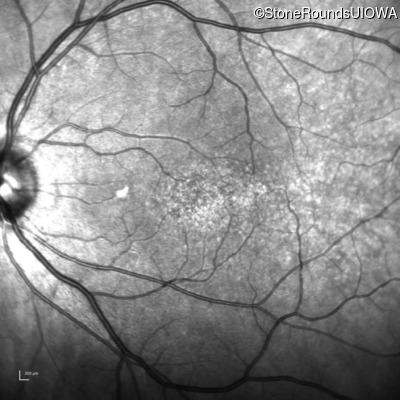

Optical Coherence Tomography - Left - 20/12.5

Exemplar / OCT Stack